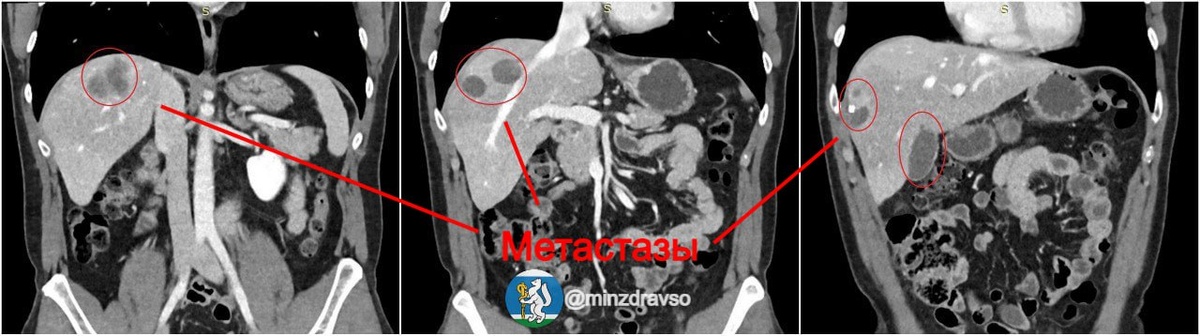

Π–ΠΈΡ‚Π΅Π»ΡŒ Π•ΠΊΠ°Ρ‚Π΅Ρ€ΠΈΠ½Π±ΡƒΡ€Π³Π° считал сСбя Π·Π΄ΠΎΡ€ΠΎΠ²Ρ‹ΠΌ, ΠΏΠΎΠΊΠ° Π² Ρ…ΠΎΠ΄Π΅ обслСдования Π² ΠΎΠ΄Π½ΠΎΠΉ ΠΈΠ· ΠΊΠ»ΠΈΠ½ΠΈΠΊ Π³ΠΎΡ€ΠΎΠ΄Π° Ρƒ Π½Π΅Π³ΠΎ Π½Π΅ ΠΎΠ±Π½Π°Ρ€ΡƒΠΆΠΈΠ»ΠΈ ΠΎΠΏΡƒΡ…ΠΎΠ»ΡŒ сигмовидного ΠΎΡ‚Π΄Π΅Π»Π° толстой кишки. ΠœΡƒΠΆΡ‡ΠΈΠ½Π° обратился Π² БвСрдловский областной онкологичСский диспансСр, Π³Π΄Π΅ послС 8 курсов Ρ…ΠΈΠΌΠΈΠΎΡ‚Π΅Ρ€Π°ΠΏΠΈΠΈ Π΅ΠΌΡƒ ΡƒΠ΄Π°Π»ΠΈΠ»ΠΈ Π½ΠΎΠ²ΠΎΠΎΠ±Ρ€Π°Π·ΠΎΠ²Π°Π½ΠΈΠ΅. πŸš‘ Однако спустя Π½Π΅ΠΊΠΎΡ‚ΠΎΡ€ΠΎΠ΅ врСмя мСтастазы снова появились. Π’ΠΎΠ³Π΄Π° ΠΏΠ°Ρ†ΠΈΠ΅Π½Ρ‚ ΠΈ ΠΏΠΎΠΏΠ°Π» Π² Π‘ΠžΠšΠ‘ β„–1, Π³Π΄Π΅ Ρ€Π΅Π½Ρ‚Π³Π΅Π½ΠΎΡ…ΠΈΡ€ΡƒΡ€Π³ΠΈ Π·Π°ΠΊΡƒΠΏΠΎΡ€ΠΈΠ»ΠΈ Π΅ΠΌΡƒ Π²Π΅Π½Ρƒ, ΠΏΠΎ ΠΊΠΎΡ‚ΠΎΡ€ΠΎΠΉ Π² ΠΏΠ΅Ρ‡Π΅Π½ΡŒ поступаСт ΠΊΡ€ΠΎΠ²ΡŒ ΠΎΡ‚ Π΄Ρ€ΡƒΠ³ΠΈΡ… Π²Π½ΡƒΡ‚Ρ€Π΅Π½Π½ΠΈΡ… ΠΎΡ€Π³Π°Π½ΠΎΠ², ΡƒΠΌΠ΅Π½ΡŒΡˆΠΈΠ² ΠΏΠΎΡ€Π°ΠΆΡ‘Π½Π½ΡƒΡŽ Π·Π°Π±ΠΎΠ»Π΅Π²Π°Π½ΠΈΠ΅ΠΌ Ρ‚ΠΊΠ°Π½ΡŒ ΠΈ ΡƒΠ²Π΅Π»ΠΈΡ‡ΠΈΠ² Π·Π΄ΠΎΡ€ΠΎΠ²ΡƒΡŽ Ρ‡Π°ΡΡ‚ΡŒ ΠΎΡ€Π³Π°Π½Π°. ☝️ Π’Π°ΠΆΠ½ΠΎ ΠΎΡ‚ΠΌΠ΅Ρ‚ΠΈΡ‚ΡŒ, Ρ‡Ρ‚ΠΎ тСхнология Β«Π£Π²Π΅Π»ΠΈΡ‡Π΅Π½ΠΈΠ΅ ΠΏΠ΅Ρ‡Π΅Π½ΠΈΒ» Π±Ρ‹Π»Π° Π²Π½Π΅Π΄Ρ€Π΅Π½Π° Π² областной Π±ΠΎΠ»ΡŒΠ½ΠΈΡ†Π΅ Ρ€ΠΎΠ²Π½ΠΎ 5 Π»Π΅Ρ‚ Π½Π°Π·Π°Π΄ ΠΈ являСтся ΠΌΠ°Π»ΠΎΡ‚Ρ€Π°Π²ΠΌΠ°Ρ‚ΠΈΡ‡Π½Ρ‹ΠΌ Π²ΠΌΠ΅ΡˆΠ°Ρ‚Π΅Π»ΡŒΡΡ‚Π²ΠΎΠΌ. Π’ ΠΈΡ‚ΠΎΠ³Π΅ ΠΎΠ±ΡŠΡ‘ΠΌ Π·Π΄ΠΎΡ€ΠΎΠ²ΠΎΠΉ части ΠΏΠ΅Ρ‡Π΅Π½ΠΈ ΠΏΠ°Ρ†ΠΈΠ΅Π½Ρ‚Π° Π·Π° Ρ‚Ρ€ΠΈ Π½Π΅Π΄Π΅Π»ΠΈ увСличился с 30% Π΄ΠΎ Π½Π΅ΠΎΠ±Ρ…ΠΎΠ΄ΠΈΠΌΡ‹Ρ… 40%, ΠΈ Π²Ρ€Π°Ρ‡ΠΈ ΡƒΡΠΏΠ΅ΡˆΠ½ΠΎ ΡƒΠ΄Π°Π»ΠΈΠ»ΠΈ ΠΏΠΎΡ€Π°ΠΆΡ‘Π½Π½ΡƒΡŽ мСтастазами долю ΠΏΠ΅Ρ‡Π΅Π½ΠΈ. Π‘ΠΎΠ»ΡŒΡˆΠ΅ подробностСй, Π° Ρ‚Π°ΠΊΠΆΠ΅ ΠΈΠΌΠ΅Π½Π° Π³Π΅Ρ€ΠΎΠ΅Π² ΡƒΠ·Π½Π°Π΅Ρ‚Π΅ Π² нашСм ΠΌΠ°Ρ‚Π΅Ρ€ΠΈΠ°Π»Π΅.

Π–ΠΈΡ‚Π΅Π»ΡŒ Π•ΠΊΠ°Ρ‚Π΅Ρ€ΠΈΠ½Π±ΡƒΡ€Π³Π° считал сСбя Π·Π΄ΠΎΡ€ΠΎΠ²Ρ‹ΠΌ, ΠΏΠΎΠΊΠ° Π² Ρ…ΠΎΠ΄Π΅ обслСдования Π² ΠΎΠ΄Π½ΠΎΠΉ ΠΈΠ· ΠΊΠ»ΠΈΠ½ΠΈΠΊ Π³ΠΎΡ€ΠΎΠ΄Π° Ρƒ Π½Π΅Π³ΠΎ Π½Π΅ ΠΎΠ±Π½Π°Ρ€ΡƒΠΆΠΈΠ»ΠΈ ΠΎΠΏΡƒΡ…ΠΎΠ»ΡŒ сигмовидного ΠΎΡ‚Π΄Π΅Π»Π° толстой кишки. ΠœΡƒΠΆΡ‡ΠΈΠ½Π° обратился Π² БвСрдловский областной онкологичСский диспансСр, Π³Π΄Π΅ послС 8 курсов Ρ…ΠΈΠΌΠΈΠΎΡ‚Π΅Ρ€Π°ΠΏΠΈΠΈ Π΅ΠΌΡƒ ΡƒΠ΄Π°Π»ΠΈΠ»ΠΈ Π½ΠΎΠ²ΠΎΠΎΠ±Ρ€Π°Π·ΠΎΠ²Π°Π½ΠΈΠ΅.

πŸš‘ Однако спустя Π½Π΅ΠΊΠΎΡ‚ΠΎΡ€ΠΎΠ΅ врСмя мСтастазы снова появились. Π’ΠΎΠ³Π΄Π° ΠΏΠ°Ρ†ΠΈΠ΅Π½Ρ‚ ΠΈ ΠΏΠΎΠΏΠ°Π» Π² Π‘ΠžΠšΠ‘ β„–1, Π³Π΄Π΅ Ρ€Π΅Π½Ρ‚Π³Π΅Π½ΠΎΡ…ΠΈΡ€ΡƒΡ€Π³ΠΈ Π·Π°ΠΊΡƒΠΏΠΎΡ€ΠΈΠ»ΠΈ Π΅ΠΌΡƒ Π²Π΅Π½Ρƒ, ΠΏΠΎ ΠΊΠΎΡ‚ΠΎΡ€ΠΎΠΉ Π² ΠΏΠ΅Ρ‡Π΅Π½ΡŒ поступаСт ΠΊΡ€ΠΎΠ²ΡŒ ΠΎΡ‚ Π΄Ρ€ΡƒΠ³ΠΈΡ… Π²Π½ΡƒΡ‚Ρ€Π΅Π½Π½ΠΈΡ… ΠΎΡ€Π³Π°Π½ΠΎΠ², ΡƒΠΌΠ΅Π½ΡŒΡˆΠΈΠ² ΠΏΠΎΡ€Π°ΠΆΡ‘Π½Π½ΡƒΡŽ Π·Π°Π±ΠΎΠ»Π΅Π²Π°Π½ΠΈΠ΅ΠΌ Ρ‚ΠΊΠ°Π½ΡŒ ΠΈ ΡƒΠ²Π΅Π»ΠΈΡ‡ΠΈΠ² Π·Π΄ΠΎΡ€ΠΎΠ²ΡƒΡŽ Ρ‡Π°ΡΡ‚ΡŒ ΠΎΡ€Π³Π°Π½Π°.

☝️ Π’Π°ΠΆΠ½ΠΎ ΠΎΡ‚ΠΌΠ΅Ρ‚ΠΈΡ‚ΡŒ, Ρ‡Ρ‚ΠΎ тСхнология Β«Π£Π²Π΅Π»ΠΈΡ‡Π΅Π½ΠΈΠ΅ ΠΏΠ΅Ρ‡Π΅Π½ΠΈΒ» Π±Ρ‹Π»Π° Π²Π½Π΅Π΄Ρ€Π΅Π½Π° Π² областной Π±ΠΎΠ»ΡŒΠ½ΠΈΡ†Π΅ Ρ€ΠΎΠ²Π½ΠΎ 5 Π»Π΅Ρ‚ Π½Π°Π·Π°Π΄ ΠΈ являСтся ΠΌΠ°Π»ΠΎΡ‚Ρ€Π°Π²ΠΌΠ°Ρ‚ΠΈΡ‡Π½Ρ‹ΠΌ Π²ΠΌΠ΅ΡˆΠ°Ρ‚Π΅Π»ΡŒΡΡ‚Π²ΠΎΠΌ.

Π’ ΠΈΡ‚ΠΎΠ³Π΅ ΠΎΠ±ΡŠΡ‘ΠΌ Π·Π΄ΠΎΡ€ΠΎΠ²ΠΎΠΉ части ΠΏΠ΅Ρ‡Π΅Π½ΠΈ ΠΏΠ°Ρ†ΠΈΠ΅Π½Ρ‚Π° Π·Π° Ρ‚Ρ€ΠΈ Π½Π΅Π΄Π΅Π»ΠΈ увСличился с 30% Π΄ΠΎ Π½Π΅ΠΎΠ±Ρ…ΠΎΠ΄ΠΈΠΌΡ‹Ρ… 40%, ΠΈ Π²Ρ€Π°Ρ‡ΠΈ ΡƒΡΠΏΠ΅ΡˆΠ½ΠΎ ΡƒΠ΄Π°Π»ΠΈΠ»ΠΈ ΠΏΠΎΡ€Π°ΠΆΡ‘Π½Π½ΡƒΡŽ мСтастазами долю ΠΏΠ΅Ρ‡Π΅Π½ΠΈ.